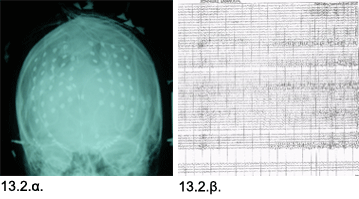

Εικόνες 13.1.α. & 13.1.β. Μαγνητική τομογραφία αναδεικνύει μικρή στρογγυλή (λευκάζουσα) περιοχή υψηλού σήματος στην έσω μετωπιαία περιοχή σε εγκάρσια (1α) και στεφανιαία προβολή (1β).

Η Μαγνητική Τομογραφία έδειξε μικρή εστία υψηλού σήματος στην αριστερή πρόσθια κεντρική έλικα, ή οποία δεν ενισχυόταν με χορήγηση παραμαγνητικών ουσιών. Η Μαγνητική Φασματοσκοπία έδειξε ήπιες αλλοιώσεις αμφοτέρων των ιπποκάμπων. Η νευροψυχολογική μελέτη έδειξε έκπτωση λειτουργιών δεξιού μετωπιαίου λοβού. Το Ηλεκτροεγκεφαλογράφημα (ΗΕΓ) ήταν φυσιολογικό.